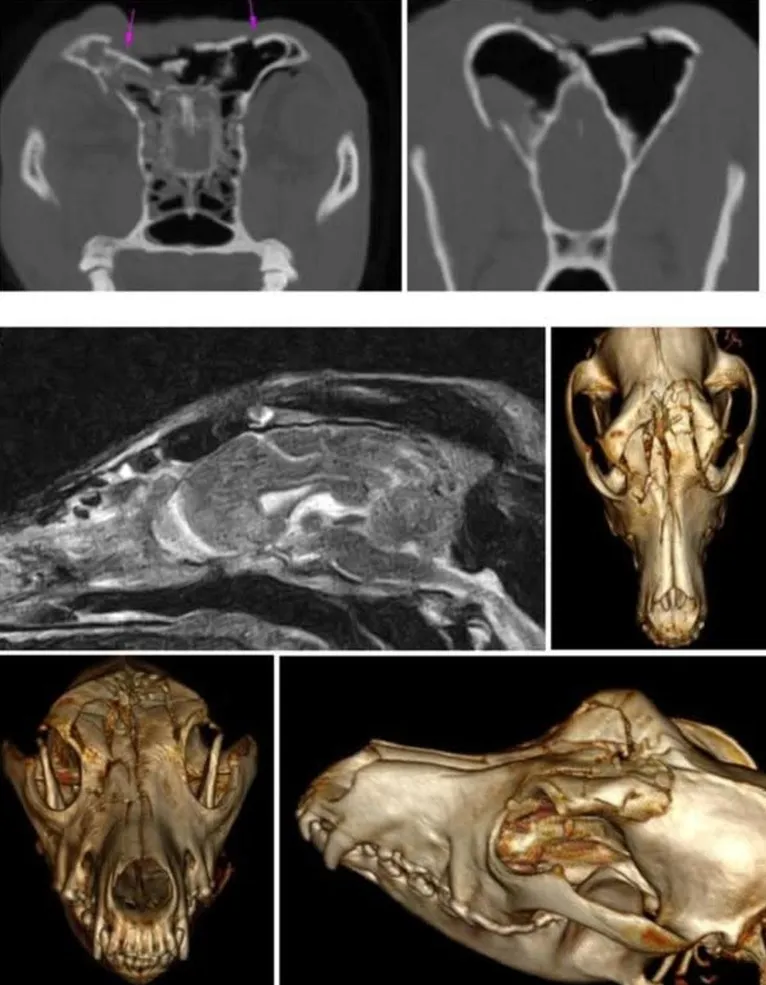

Mint írták, március 21-én, szombaton hajnalban egy férfi kegyetlenül leütött egy felé ballagó kutyát az erdőben. A szelíd eb nem volt pórázon, de csak barátkozni ment oda a járókelőkhöz. Néhány méterre álló gazdája hiába kiabált, hogy az állat nem bánt senkit, a támadót ez nem érdekelte, és egy hatalmas doronggal szétverte a négylábú fejét, majd feleségével odébbállt.

A 14 éves Henna az ütéstől azonnal összeesett, szilánkosra tört a homlokcsontja, és csontszilánk került az agyába, illetve az orrüregébe is.

A vizslát azóta kiengedték a kórházból, gazdái bizakodóak a felépülését illetően, bát tudják, hogy akár szepszis vagy epilepsziás roham is felléphet kedvencüknél az elkövetkező időszakban.